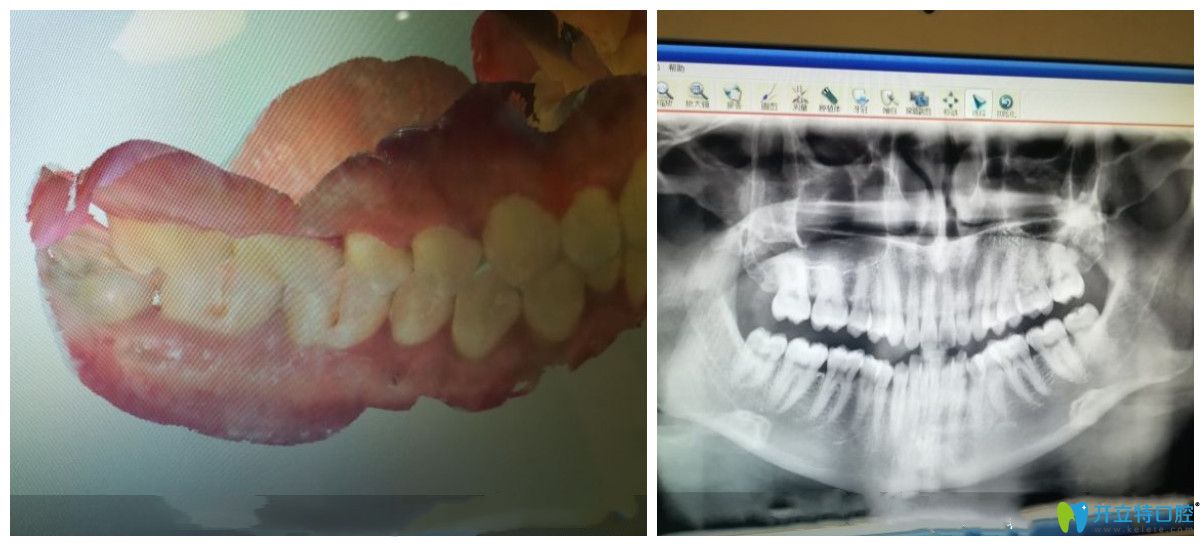

在成都圣貝口腔做隱形矯正前檢查圖